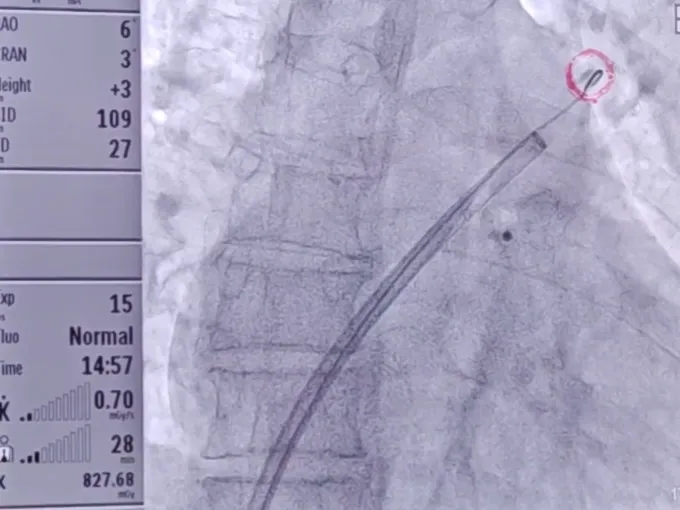

术中DSA肝位造影并测量心耳大小:菜花型左心耳

开口24.3mm,深度24.7mm

该心耳为菜花型,此类心耳一般多为囊袋状多分叶,术前造影评估远端梳状肌较为发达,开口24.3mm,深度24.7mm,深度足够,建议选择LAFDQ-26封堵器进行封堵。

封堵器展开后造影

封堵器完全展开,封堵器未露肩

封堵器稳定封堵,无残余分流

压缩比10.95%

Lefort封堵器评估符合PASS原则,释放封堵器,封堵器位置稳定且未见残余漏

术前结合CT以及术中造影评估左心耳开口24.3mm,深度24.7mm,术中考虑心耳开口和深度充足,可利用心耳空间进行退鞘释放封堵器,使封堵器完全封堵左心耳。术中调整封堵器在心耳内的位置形态,确保封堵器放置位置合适,且牵拉稳固,术后封堵器形态完整,未见残余漏。本病例展开后即刻造影,平口封堵,上下缘不留残腔。封堵器压缩比为10%,压缩合适,术中符合PASS原则,释放封堵器,术后封堵器稳固锚定在心耳壁,封堵器与心耳紧密贴合,无过度扩张风险,显著提升封堵完整性。